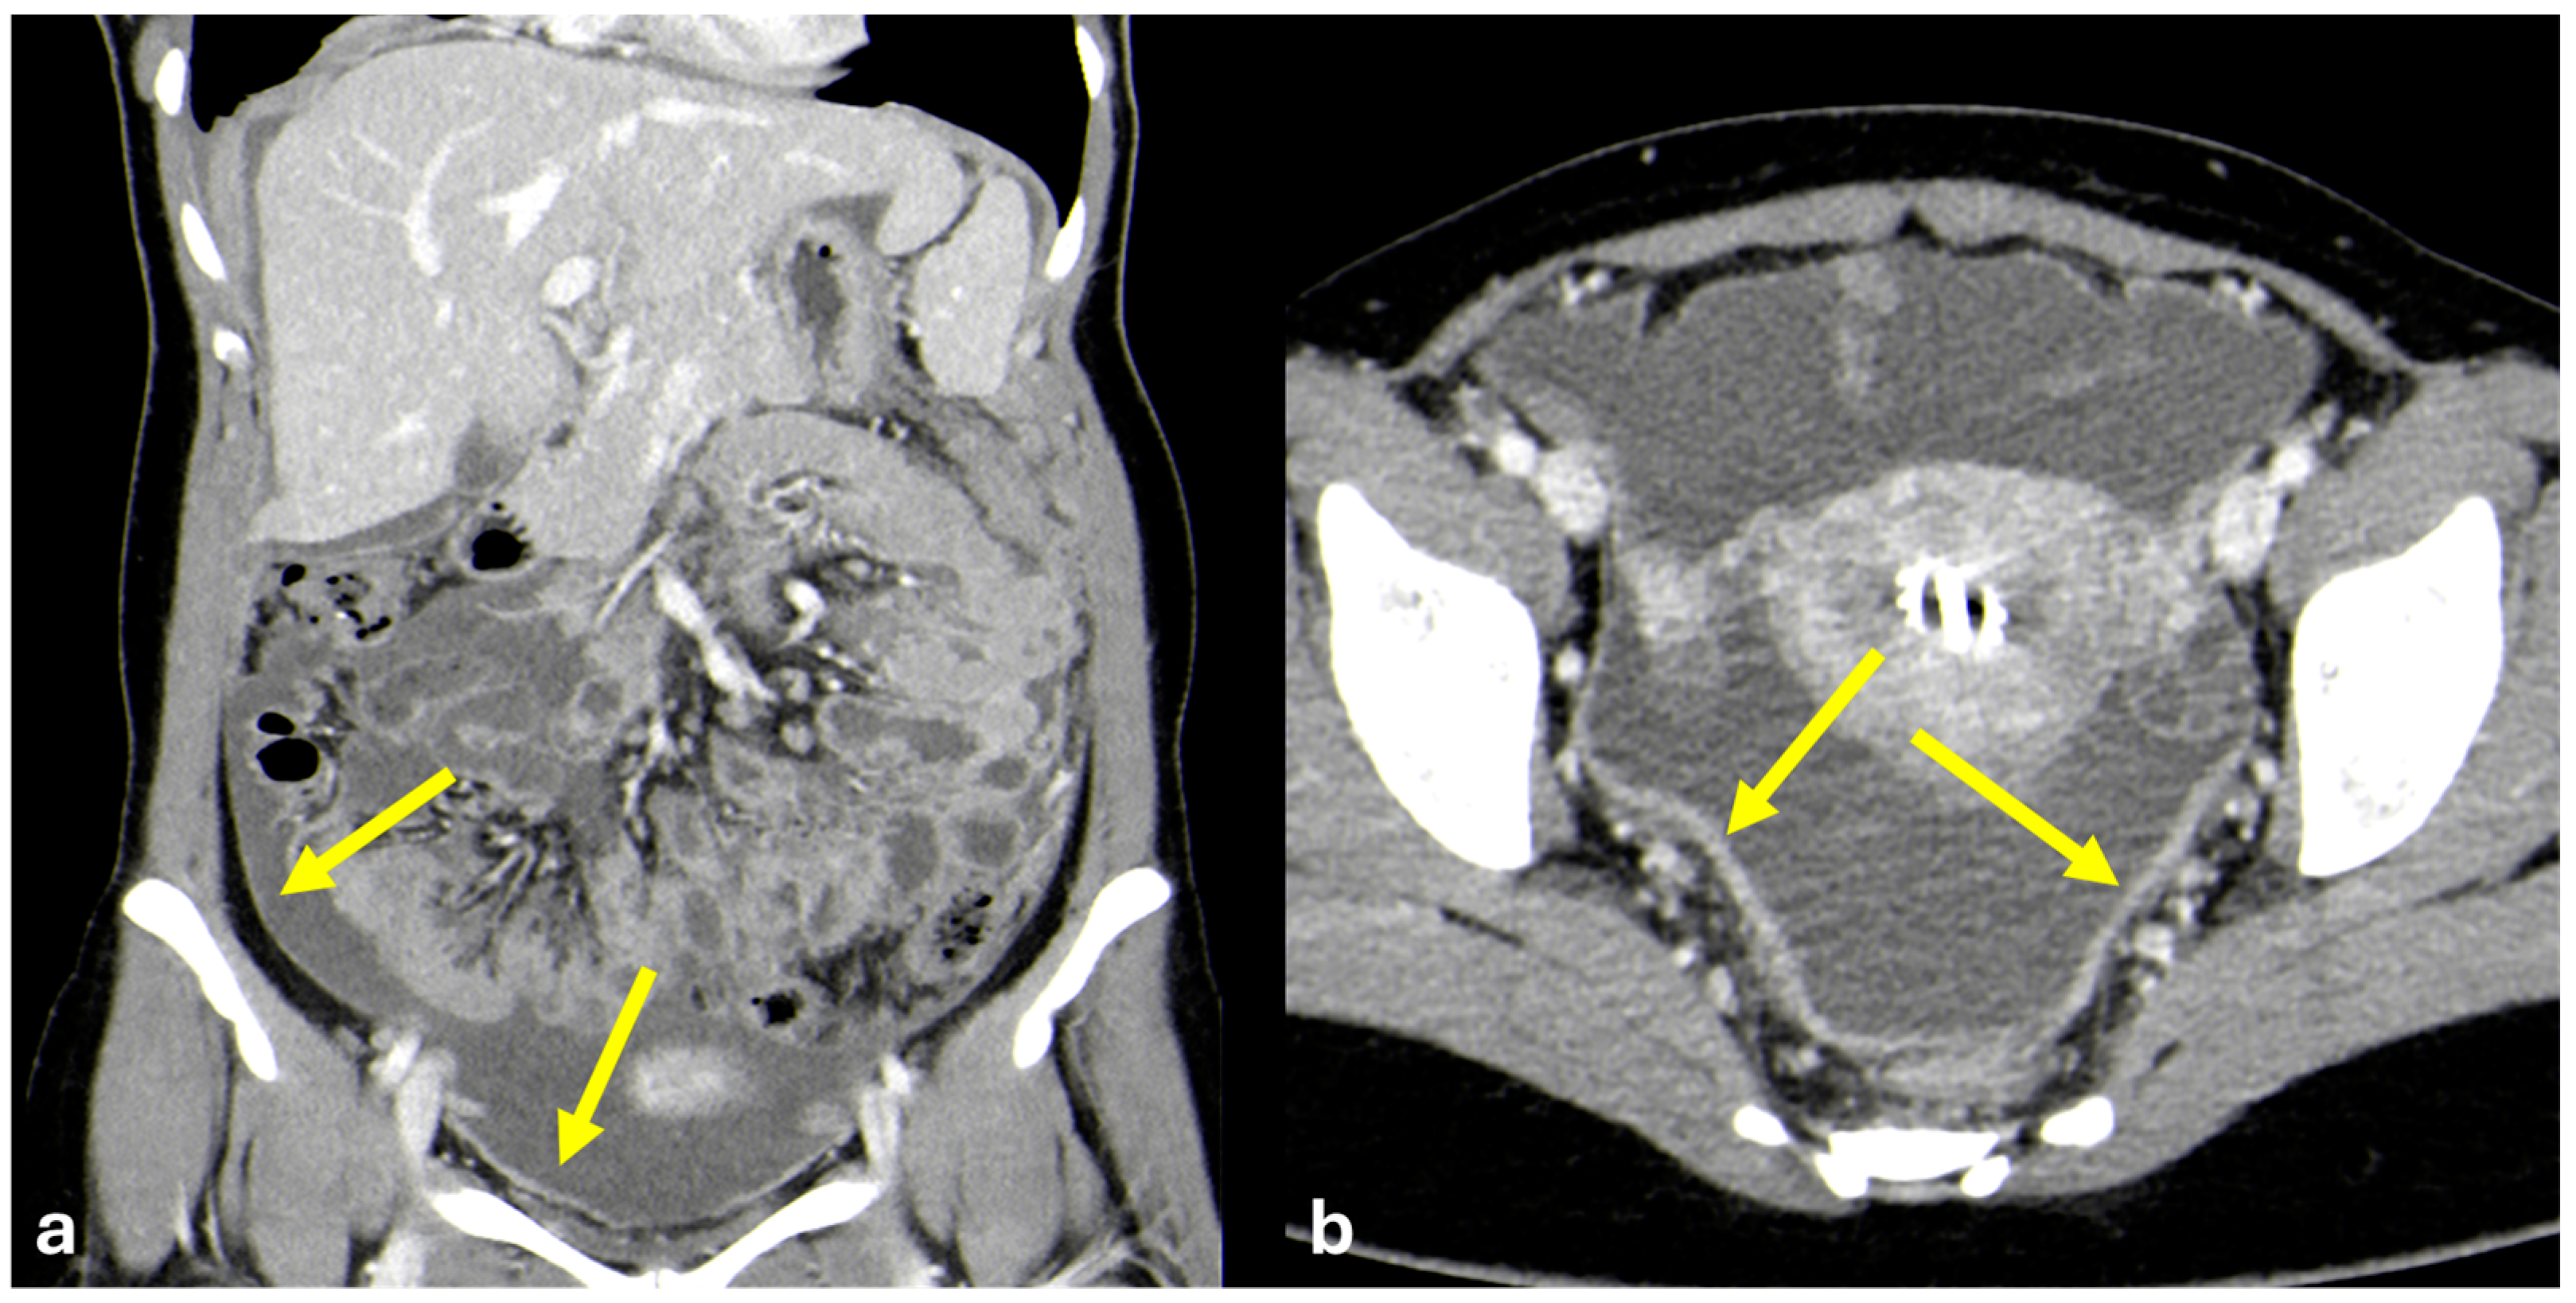

- Nodular pattern: nodules with a diameter > 5 mm (Figure 2a);

- “Omental cake”: nodular thickening of the omentum (Figure 2b);